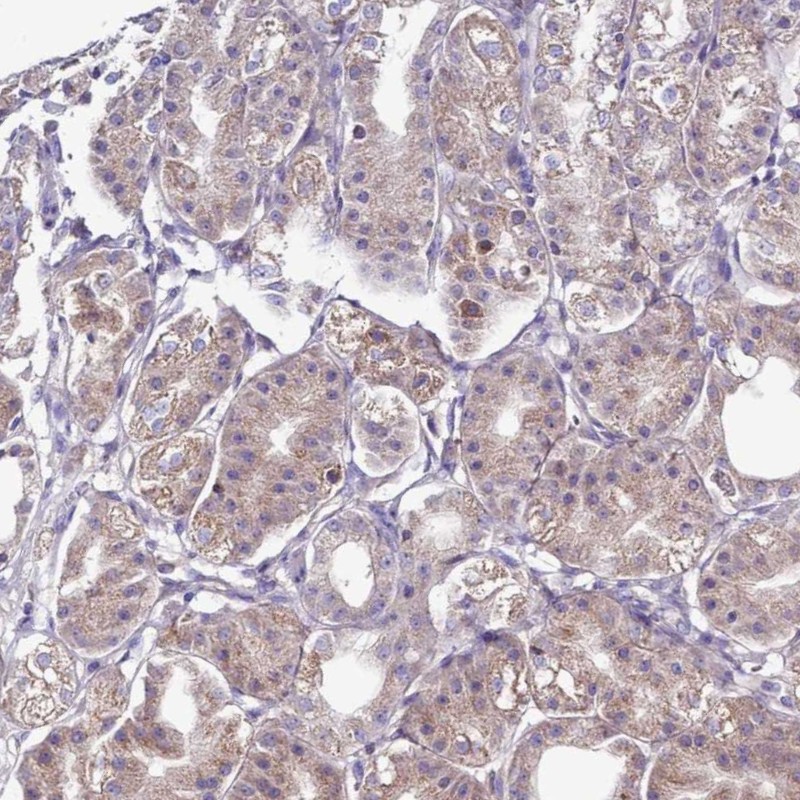

Immunohistochemical staining of human stomach shows moderate cytoplasmic positivity in glandular cells.